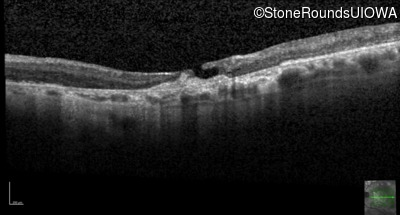

Optical Coherence Tomography - Right - 20/125 -2

Exemplar / OCT Stack